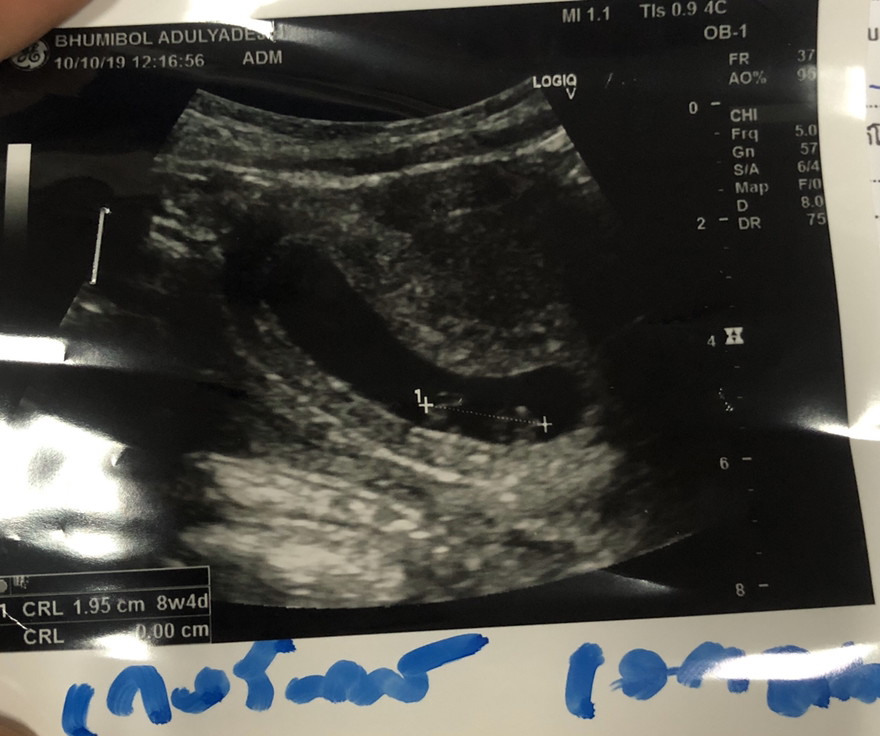

ทีมสิงหาเหมือนกันค่ะ 8w 4d ค่ะ🥰

10w2d แล้วค่ะ #ทีมเดือนสิงหา😊